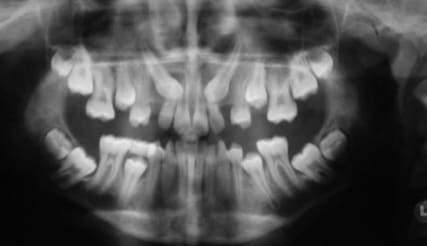

que feriez vous dans ce cas? extraire la 37 et tracter la 38 en position de la 37 ou preserver la 37 qui semble-t-il a un pronostic endodontique defavorable!

quel est le meilleur rapport benefice risque?

Extraire la 37 sans hésiter et tenter ta chance pour le tractage de 38.

Quel pronostic concernant la traction d'une sagesse quasi horizontale comme sur la pano?

La question m'interpelle, je suis en général favorable aux extractions/tractions des 8, mais c'est typiquement le cas ou j'ai un doute...

Racines fines et longues et fragiles, risque de fracture, proximité du canal dentaire, racine de la 38 fermées, mauvaise position de la 38 qui va gêner la cicatrisation osseuse, et si complications -> obligation d'extraire la 38, mouvement othodontique très important dans un os néo formé pauvre, risque important de fonte de la racine 38, longueur d'un traitement qui donnera envie de l'arrêter.

Vu l'état de la denture sur la pano, il faut mieux commencer par des choses simples, puis réévaluer la motivation, avant de se lancer dans un ttt multiattaches potentiellement cariogène.

A mon sens, on ne peut pas juger du pronostic de la 37 sans y être allé voir.

je m'occuperais d'abord de l'hygiène et des caries avant de réfléchir à l'ortho.

Verdict des prof, redresser cette dent est parfaitement faisable mais :

- surement plus d'un ans de traitement

- risque de résorption radiculaire laissant la dents avec un rapport couronne racine défavorable sur le long terme

Eux ils peuvent faire mais ça ne leur semble pas la meilleur option pour le patient, si il avait était plus jeune ça se serait discuté.

jeudi matin j'extraierai la 37 ensuite on essaiera de faire qq chose avec la 38 le patient comprend que l'issue est aleatoire donc si ca marche pas je lui poserai un implant.